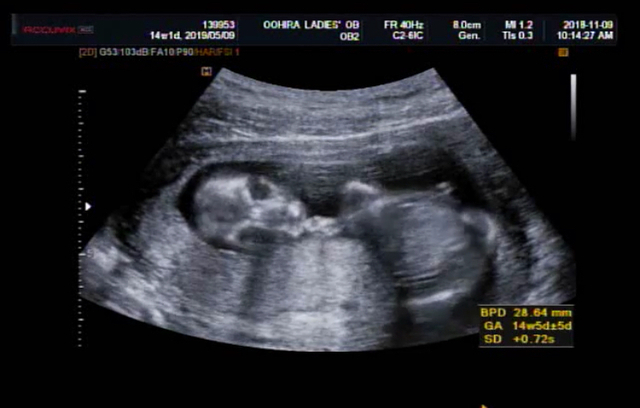

14週1日(14w1d・男の子)|なかこ さん(35歳)

エコー写真撮影時のエピソード:

エコーを主人と一緒に見ながら、説明を受けました。だんだんはっきりと人間の形がわかってきて、まだ週数が浅いのにすごいなぁと感動しました。

なんだか、まん丸い頭に目と口もわかり、お腹もまん丸で、エコー写真なのにすごくかわいいなと感じました。

冷静になって見ると、少しガイコツみたいで怖い?!なんて、思いながらすでに親バカだなぁとにやけて、何度も見返していました。